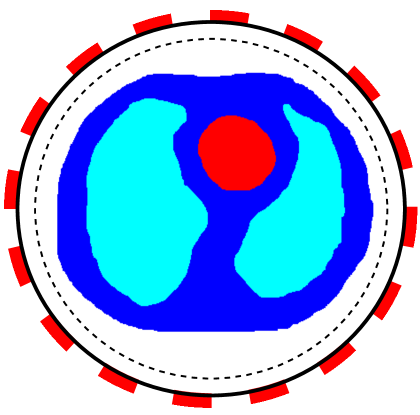

The first example is a heart-lung model [35], see Figure 1(a). The considered three tissues are heart (red, ), lung (cyan, ), and soft-tissues (blue, ). The model is placed into a circular region with a background material (white, ) and a radius .

To work with CEM and LM-SCEM, 16 electrodes (red rectangles shown in Figure 1) are uniformly attached on the boundary (solid black lines). The section occupied by each electrode has the same central angle in both the heart-lung and human-brain models. The following computations assume that the conductivity in a small region close to boundary (between solid and dashed black lines) is known. The distance between the solid and dashed lines is given by . This known region helps to improve the convergence of the algorithm. Three current patterns based on Fourier basis functions are used in the computations, which are for , and . The regularization parameter is chosen to decrease exponentially, and with . In what follows, a relatively large value is given to , and a value close to 1 is given to for a slow decreasing of to ensure the convergence of the iterations.